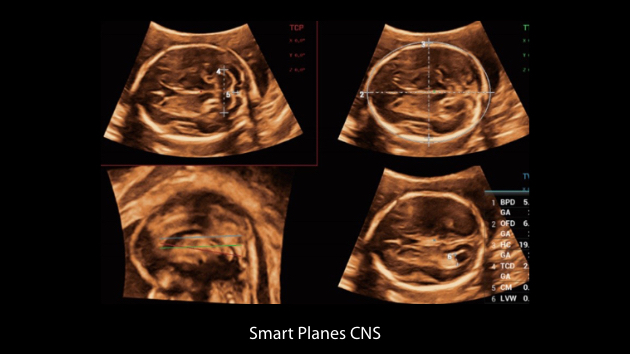

The Nuewa I9 Elite Edition, dedicatedly designed for women and neonatal healthcare, providing an innovative experience from inside out. These innovations are developed based on in-depth insights into complex clinical scenarios, providing accurate and timely answers as well as outstanding efficiency and remarkable user experience